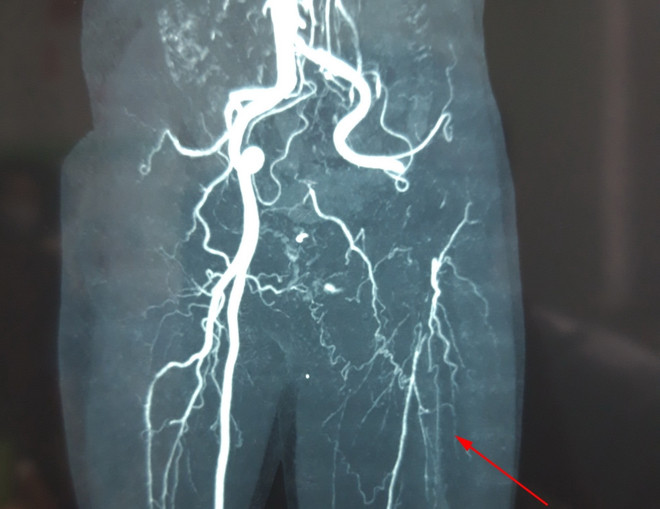

Cảnh báo nguy cơ tắc động mạch chi cấp tính khi bị tê bì chân tay ảnh 1Hình ảnh chụp MSCT mạch máu của ông N. bị tắc. (Ảnh: TTXVN phát)

Qua thăm khám và kết quả chụp MSCT, các bác sỹ chẩn đoán ông N bị tắc hoàn toàn động mạch chậu, đùi, khoeo và cẳng chân trái do xơ vữa mạch máu và tình trạng tăng đông máu hình thành huyết khối.

Các bác sỹ nhanh chóng phẫu thuật cấp cứu cho người bệnh. Trong hơn 1 giờ, bác sỹ dùng ống thông chuyên dụng lấy ra toàn bộ đoạn huyết khối dài 80cm trong mạch máu.